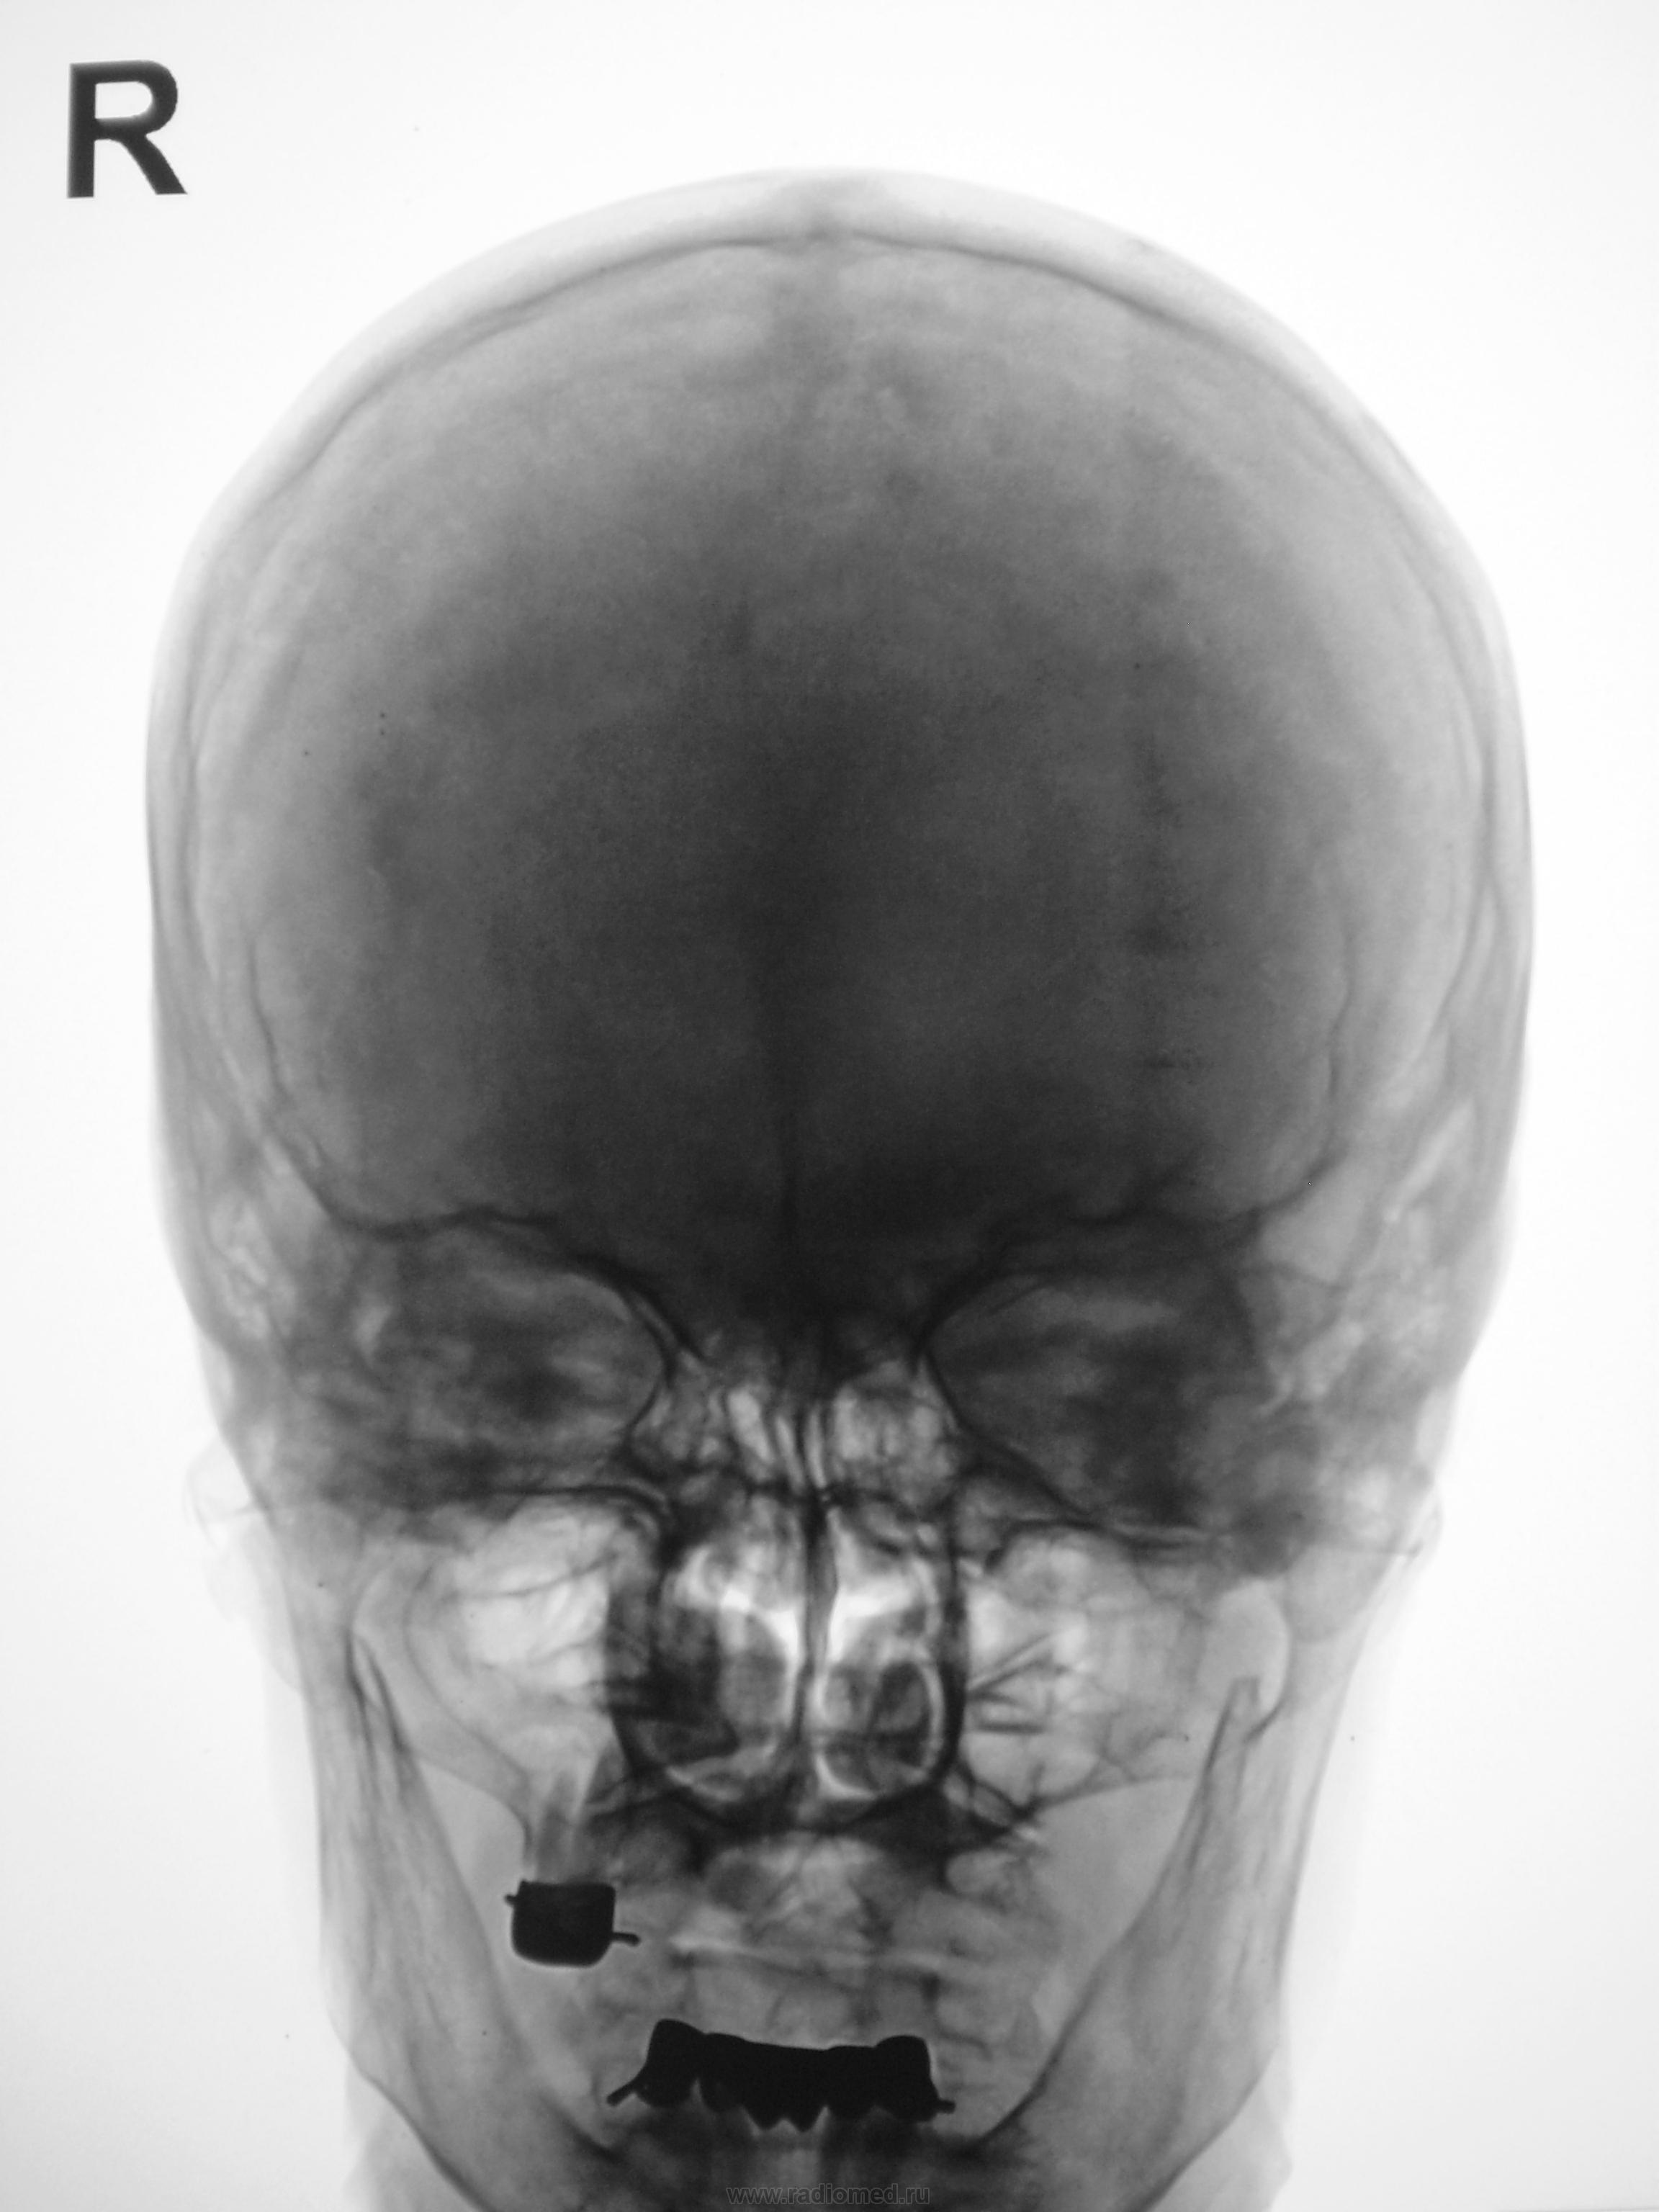

Снимки черепа. И? Что Вам подсказать, Валентин Львович?

Акцент на обызвествлении. Осталось найти его на прямом снимке. В любом случае, одной краниографией не ограничиться. Патология имеется, а насколько она клинически значима, это решит КТ.

По боковому снимку, в проекции теменной области плотная округлая тень. Для уточнения характера изменений рекомендованя МРТ головы.С какой целью назначалось исследование?

Ответ таков: на снимках черепа есть подозрение на патологическое обызвествление. А теперь давайте гадать, что это. Обызвествление серпа или кальцинаты интракраниально. 50/50

Согласна, обызвествление, вероятно серповидного отростка.

Полностью согласен с коллегами!Обызвествление!

Я надеялся, что обызвествление серпа, даже пусть локальное, лучше должно быть видно на рентгенограмме, произведенной в прямой проекции...

Странное обызвествление для серповидного отростка - круглое такое... (Выше - он, согласен, а здесь - ?..) А в прямой проекции оно проекционно сливается с озерцом или растворилось в эмиссариях, надо полагать?..